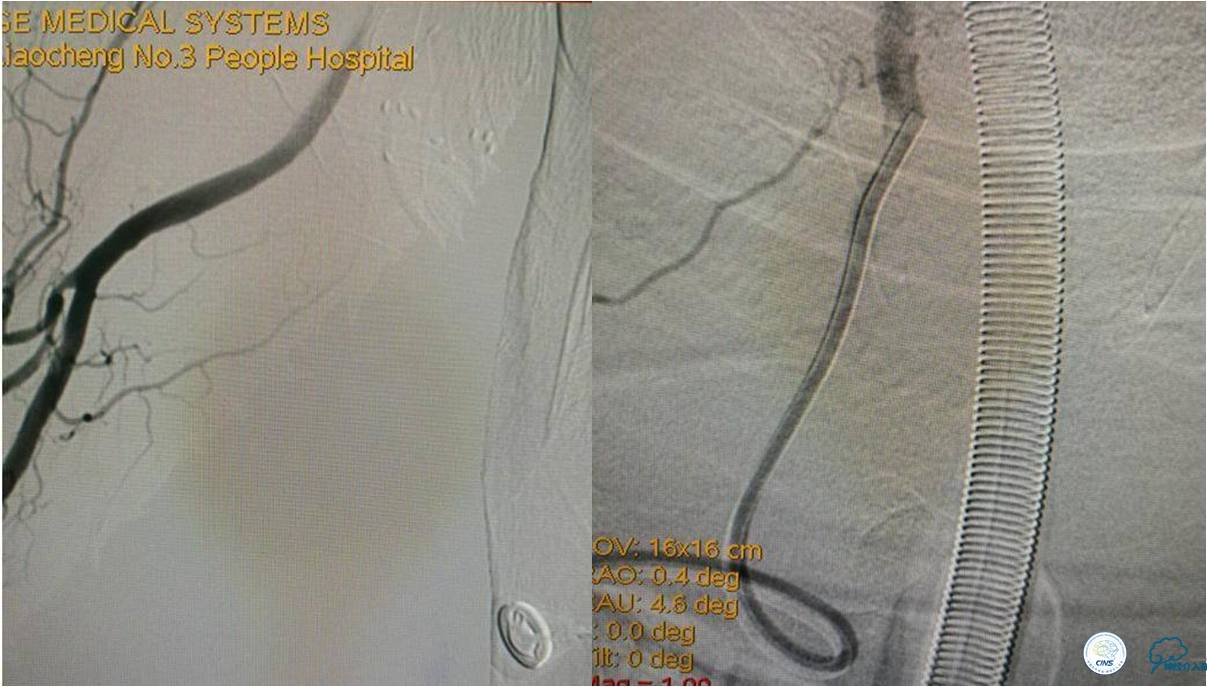

》DSA资料(经桡动脉,5F导引导管)

》DSA资料(右侧椎动脉)

★后循环取栓病人,若股动脉入路较差,可以考虑经桡动脉进行。